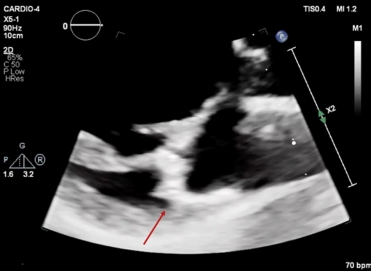

TTE was performed. The LV had a normal size, however, left ventricular ejection fraction (LVEF) was mildly impaired (48%) with mild longitudinal dysfunction (GLS -16,6%). The mitral valve appeared thickened and redundant, with bi-leaflet prolapse and mild regurgitation. MAD was seen, with a length of 4-5mm measured in mid-systole.